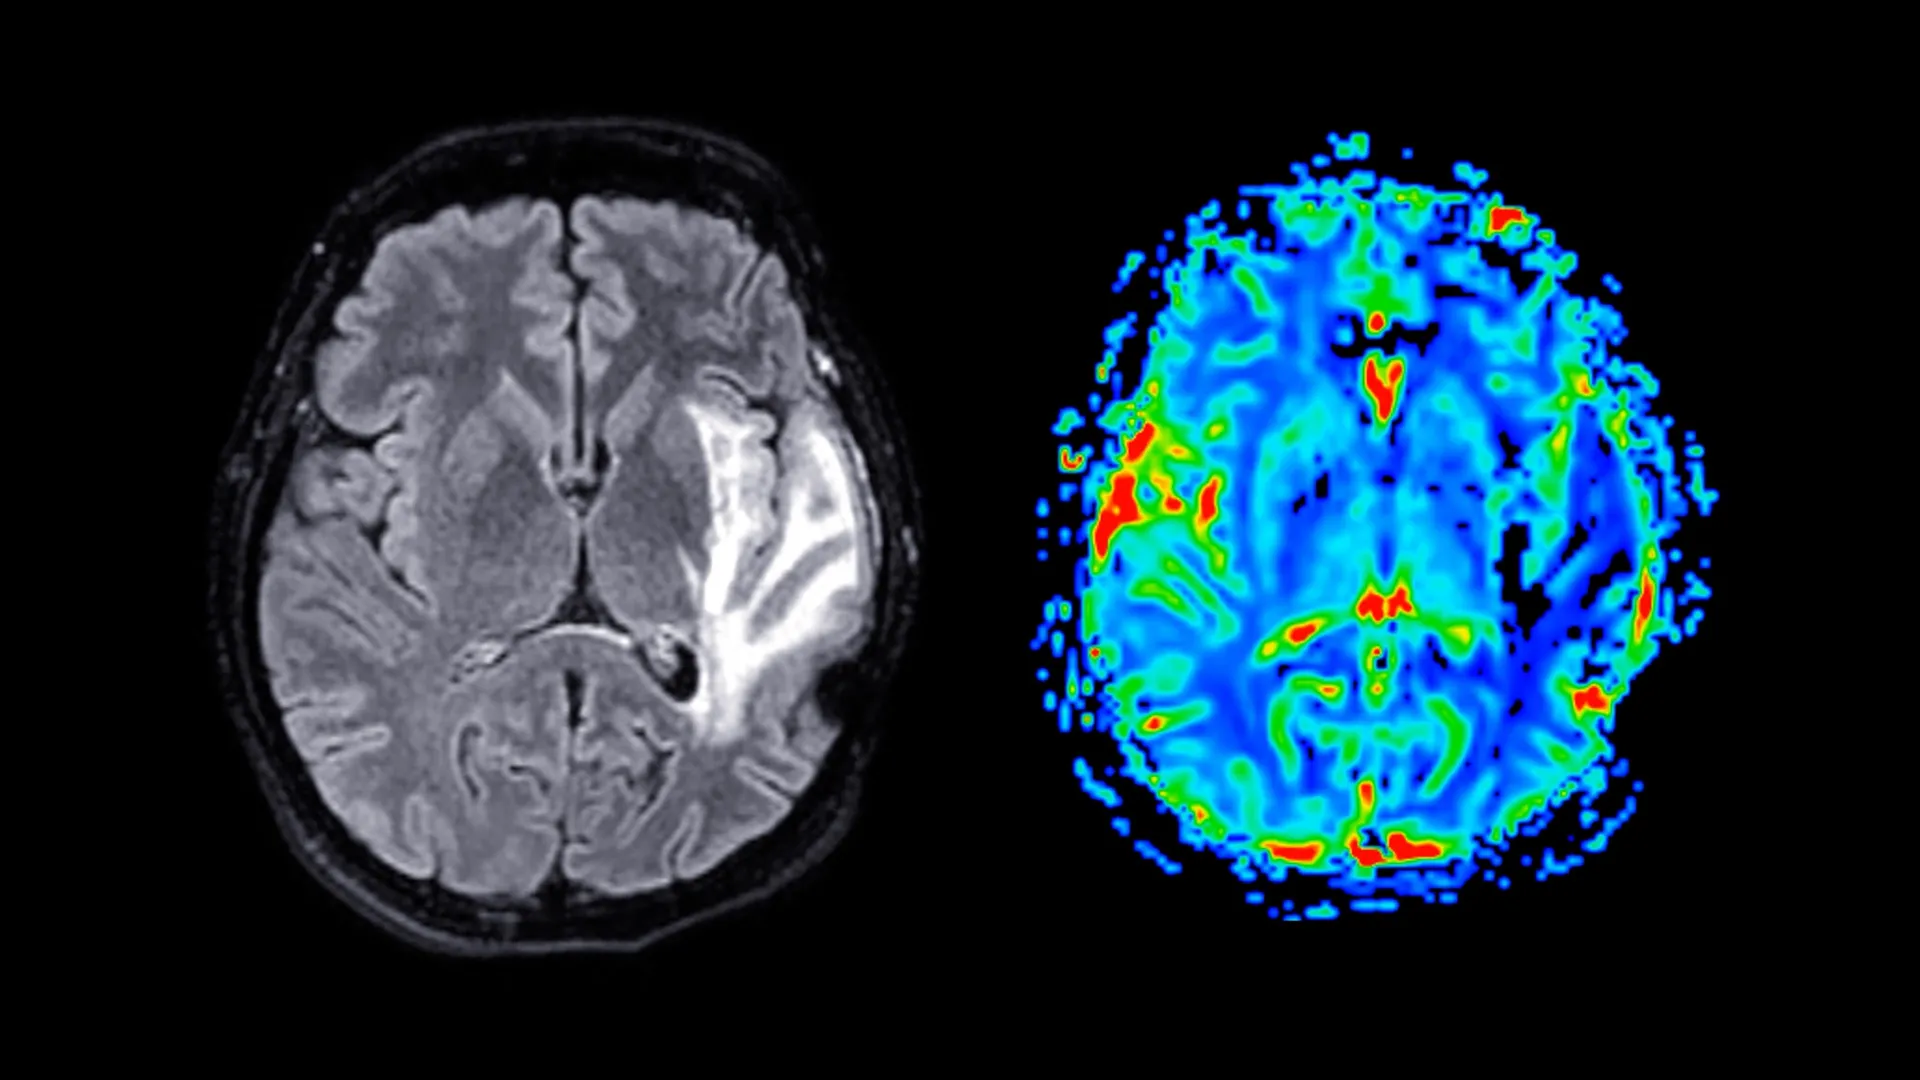

The study’s methodology involved the administration of detailed questionnaires designed to capture information pertaining to menopausal symptoms, psychological health status, established sleep habits, and general health indicators. A subset of participants also engaged in a series of cognitive assessments designed to evaluate specific aspects of memory and the speed of motor responses. Furthermore, a significant group of approximately 11,000 women underwent magnetic resonance imaging (MRI) scans, providing invaluable high-resolution anatomical data of their brains, enabling the researchers to identify and quantify structural discrepancies.

Neuroimaging investigations revealed that post-menopausal women exhibited substantial reductions in grey matter volume, a finding that remained consistent regardless of their HRT usage status. Grey matter, the brain’s primary processing center, comprises neuronal cell bodies and is instrumental in information processing, motor control, and the regulation of memory and emotional responses. The regions most notably affected by this volume reduction included the hippocampus, crucial for memory formation and consolidation; the entorhinal cortex, serving as the primary conduit for information transfer between the hippocampus and other brain areas; and the anterior cingulate cortex, a key component of the brain involved in emotional regulation, decision-making, and attentional focus.